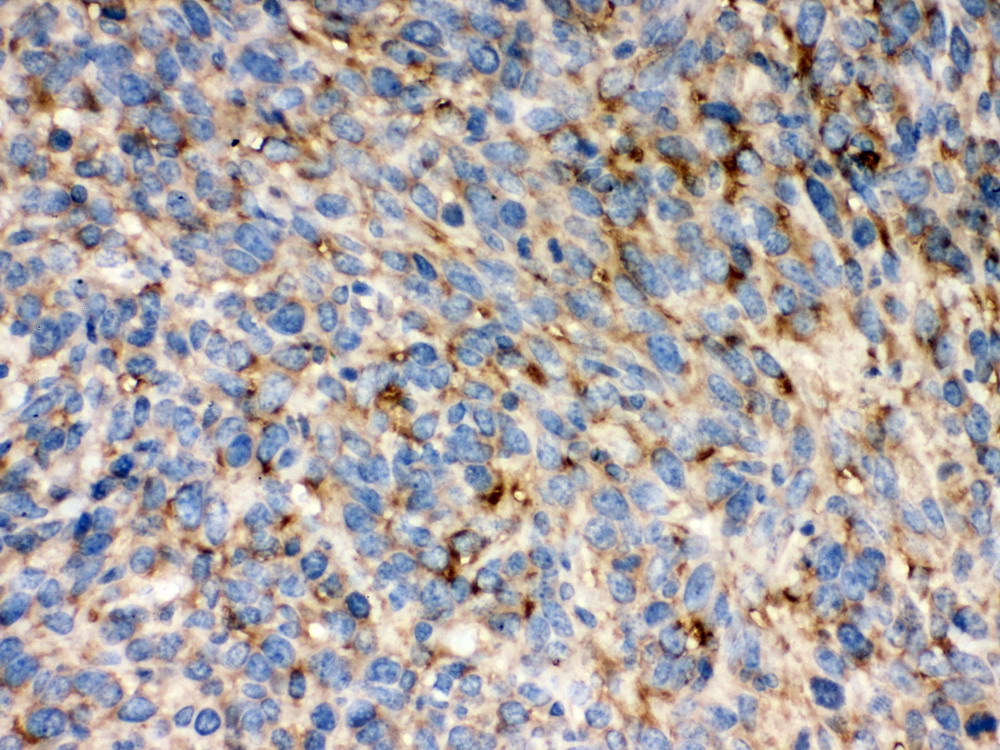

IHC analysis using anti- KDR antibody (BM0864). detected in paraffin-embedded section of human lung cancer tissue. Biotinylated goat anti-mouse IgG was used as secondary antibody. The tissue section was developed using Strepavidin-Biotin-Complex (SABC) (Catalog # SA1021) with DAB as the chromogen.